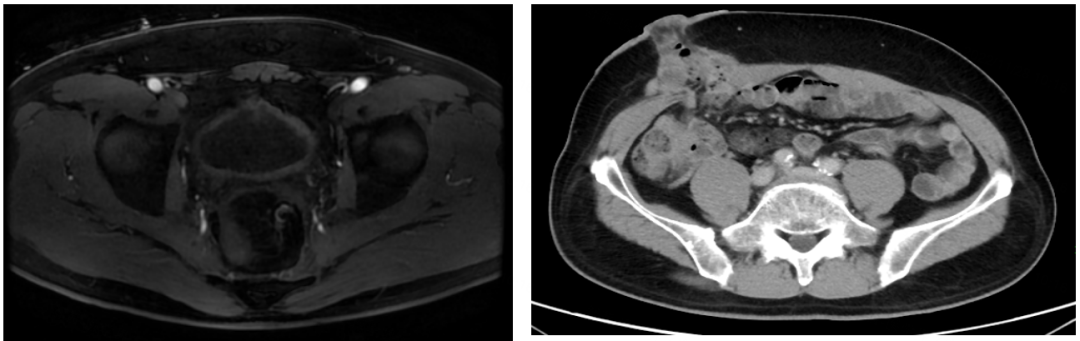

2021年5月13日开始每3个月复查1次,疗效评估均为持续PR。

图7 盆腔CT